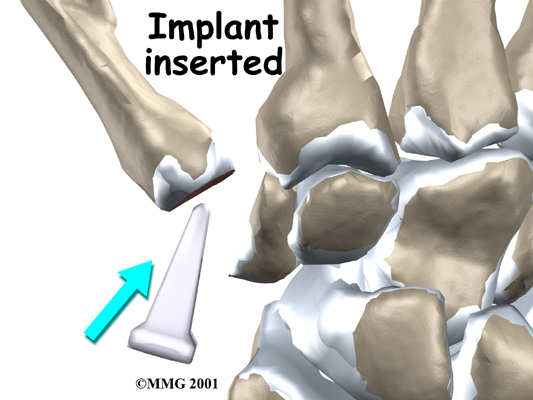

A burr (a small cutting tool) is used to make a canal into the bones that form the thumb joint. The surgeon sizes the stem of the prosthesis to ensure a snug fit into the canal and inserts it. When the new joint is in place, the surgeon wraps the joint with a strip of nearby tendon. This gives the new implant some added protection and stability.

A burr is used to make a small notch, or canal, in the ends of the two bones. The surgeon shapes the notch so the ball-shaped implant will fit snugly in the joint. The implant is placed between the ends of the shaped bones.

View animation of stem sizing and insertion